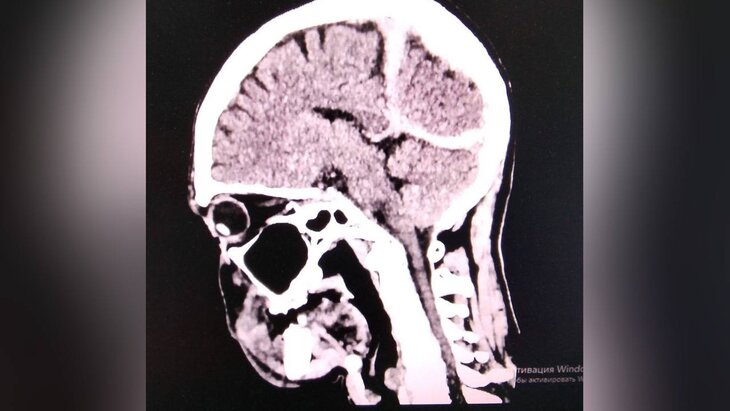

Фото: телеграм-канал "Минздрав Приморья"

Пострадавшего обнаружили местные жители, после чего его в тяжелом состоянии экстренно доставили в Спасскую городскую больницу. Помимо переохлаждения, врачи выявили у мужчины рану головы, ушиб головного мозга и субдуральную гематому.